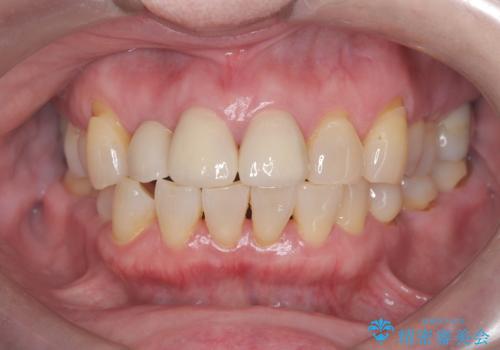

- 前歯の隙間とへこみが気になり、特に舌で触ると気になってストレスを感じるとのことで来院された患者様です。

上下ともに軽度の叢生があり、下顎がやや前突傾向にあったため、本来であれば矯正治療が第一選択となります。矯正によって下の前歯を後方に移動させることで、咬み合わせの改善とともに前歯のデコボコも整えることができます。

しかし、患者様はワイヤー矯正もマウスピース矯正も「絶対にしたくない」との強いご希望がありました。